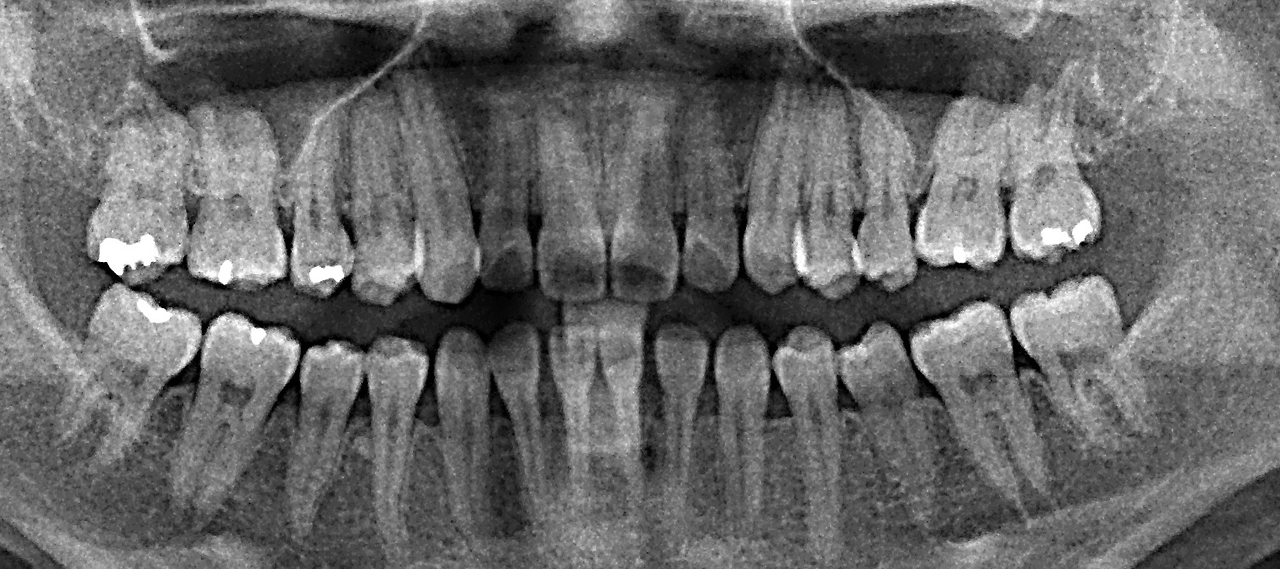

치아 교정

남보다 늦은 치아 교정을 시작했다.

친구들은 교정을 끝내고도 한참이 지난 시점에 치아교정을 시작하게 됐다. 10여 년 전만 해도 분명 양악 수술이 아니면 치료가 불가능했었는데, 세월이 흐르고 의학도 발달해서 내 치아도 교정으로 부정 교합을 맞출 수 있게 되었다. 치아 교정은 내 기대보다 훨씬 불편해서, 10여 년 전 안경을 쓰던 때를 생각나게 했다. 라식 수술 전까지는 눈이 나빠 항상 안경을 쓰고 생활을 했었다. 나는 안경의 도움 없이는 앞을 보지 못하는 사람이었다.

교정을 시작할 때에도 라식을 준비할 때도 의료 보험이 되는지 가장 먼저 알아봤다. 하지만 매번 나라가 정한 기준에는 조금씩 못 미쳐서 비보험으로 수술을 진행했다.

조금만 더 어긋났다면 나는 의료보험 대상자가 되었겠지. 조금만 더 나빴다면 나는 국가가 인정한 몸이 불편한 사람이 될 수 있었다.